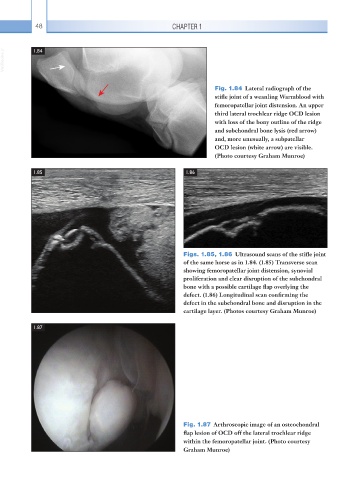

Fig. 1.84 Lateral radiograph of the

stifle joint of a weanling Warmblood with

femoropatellar joint distension. An upper

third lateral trochlear ridge OCD lesion

with loss of the bony outline of the ridge

and subchondral bone lysis (red arrow)

and, more unusually, a subpatellar

OCD lesion (white arrow) are visible.

(Photo courtesy Graham Munroe)

Figs. 1.85, 1.86 Ultrasound scans of the stifle joint

of the same horse as in 1.84. (1.85) Transverse scan

showing femoropatellar joint distension, synovial

proliferation and clear disruption of the subchondral

bone with a possible cartilage flap overlying the

defect. (1.86) Longitudinal scan confirming the

defect in the subchondral bone and disruption in the

cartilage layer. (Photos courtesy Graham Munroe)

Fig. 1.87 Arthroscopic image of an osteochondral

flap lesion of OCD off the lateral trochlear ridge

within the femoropatellar joint. (Photo courtesy

Graham Munroe)